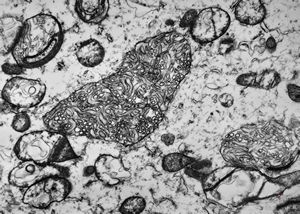

F,50y. | progressive multifocal leukoencephalopathy- viral particles in a glial cell

F,50y. | progressive multifocal leukoencephalopathy- viral particles in a glial cell

F,50y. | progressive multifocal leukoencephalopathy- viral particles in a glial cell